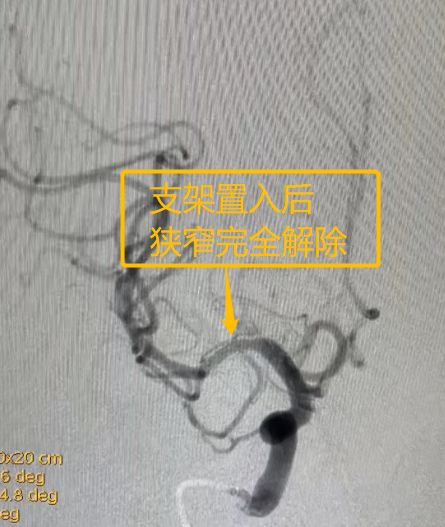

王红霞非常理解老人的心情,马上为他办理了入院手续,并且及时完善了颅内动脉支架术前检查,并邀请神经外科副主任吕恩振会诊,为患者制定详细的手术计划和应急预案。于2023年2月3日在全麻下为患者放置了一枚颅内支架。“由于患者血管基础很差,给手术过程带来了不小的难度。”吕恩振说道,“但是我们神经科团队凭借丰富的临床经验和精湛的医术,为患者完美的解决了颅内动脉严重狭窄的问题,术后第三天患者就痊愈出院了。”

患者儿子激动地说道:“我们家的老人年前就发病了,在诊所输液效果很差,来到七院神经内科,王红霞大夫诊断的非常准确,老人脑梗死症状恢复的很快,神经科大夫和护士非常尽心尽责。这不,过了年就来找吕主任放支架,手术做的很成功!经过一波三折的就医过程,一颗悬着的心终于放下了。”